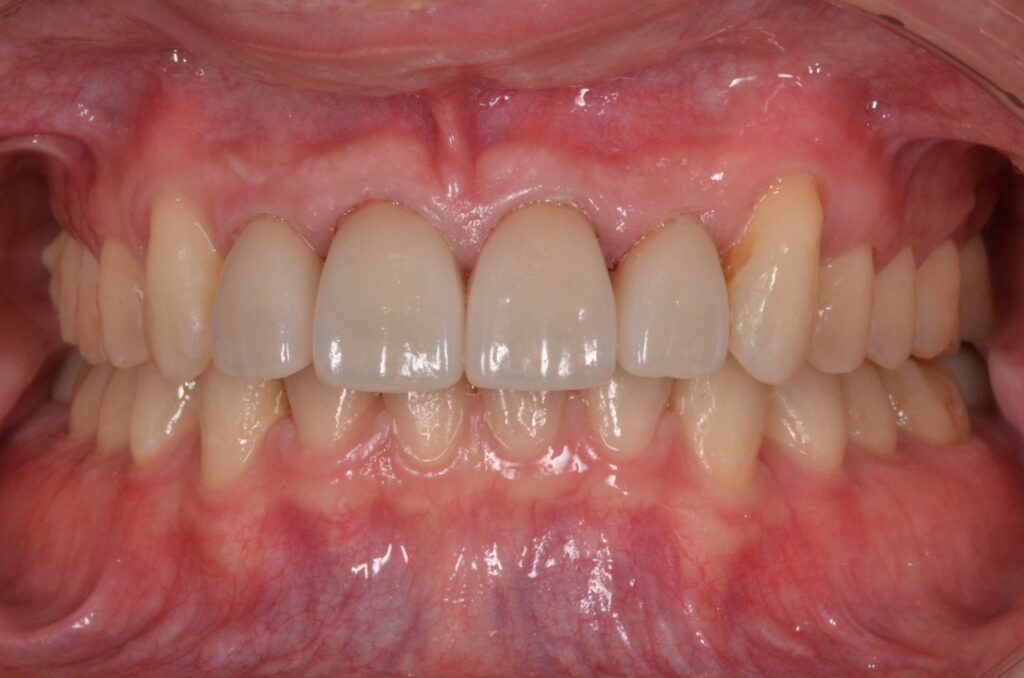

マウスピースでゆっくりと歯並びが治ったので、周りに気づかれずに済みました。治療後に以前の写真を見て驚きました。

| 治療方法 | マウスピース矯正治療(インビザラインシステム) セラミック治療 |

| 治療期間 | 2年 |

| 治療費 | マウスピース矯正治療 125万円 セラミック治療 20万円/1本 |